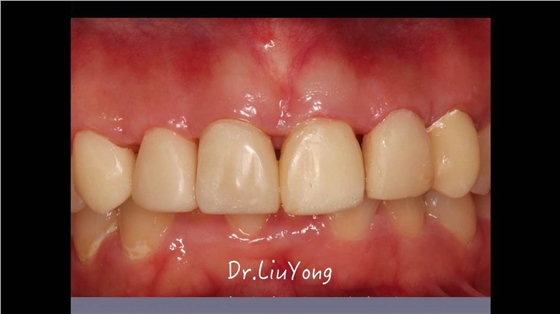

嚴重破壞生物學寬度,根尖瘺管,重行根管治療,第一次冠延長建立唇腭側及鄰面BW, 術后牙齦扇貝形差,齦乳頭黑三角,再次行美學冠延長,建立牙齦扇貝形,手術免費, 患者因經濟原因只能選擇鑄樁及鈷鉻合金烤瓷冠。終于完工